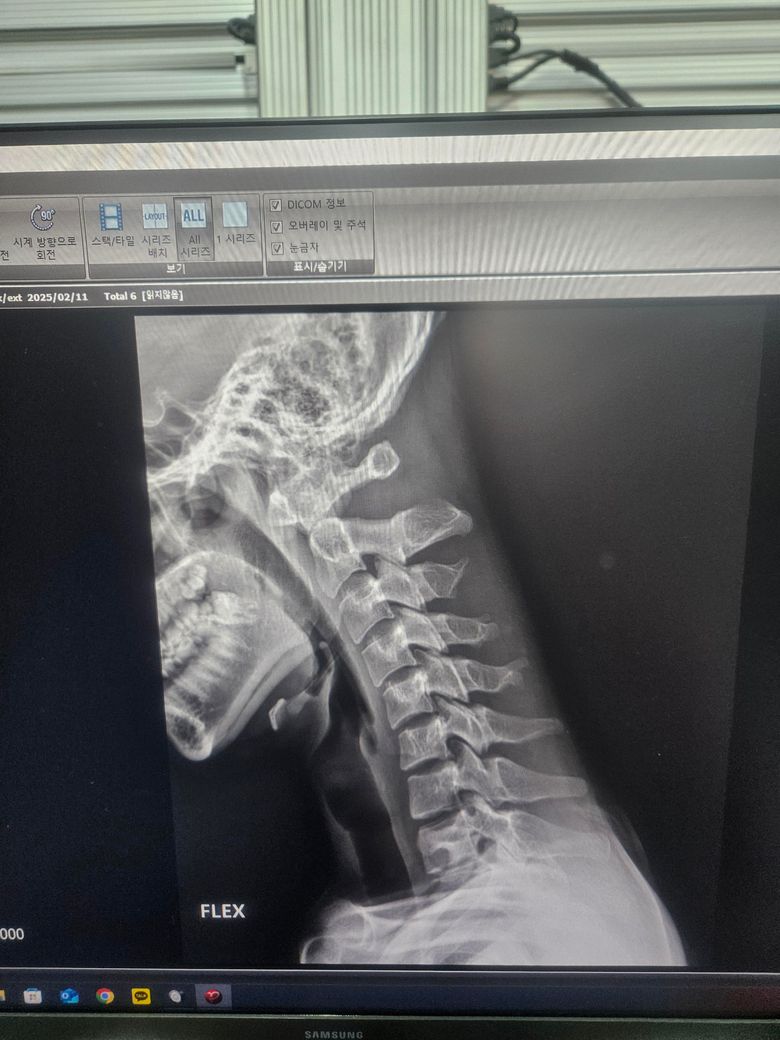

경추 굴곡 시 상부 경추 중 1, 2 번의 과운동성이 발생하는 것 같구요.

경추는 1, 2, 3번이 상부 경추 4, 5, 6, 7번이 하부경추로 나눠지며

움직임 역시 상부경추는 움직임 ↑, 하부경추는 안정성 ↑